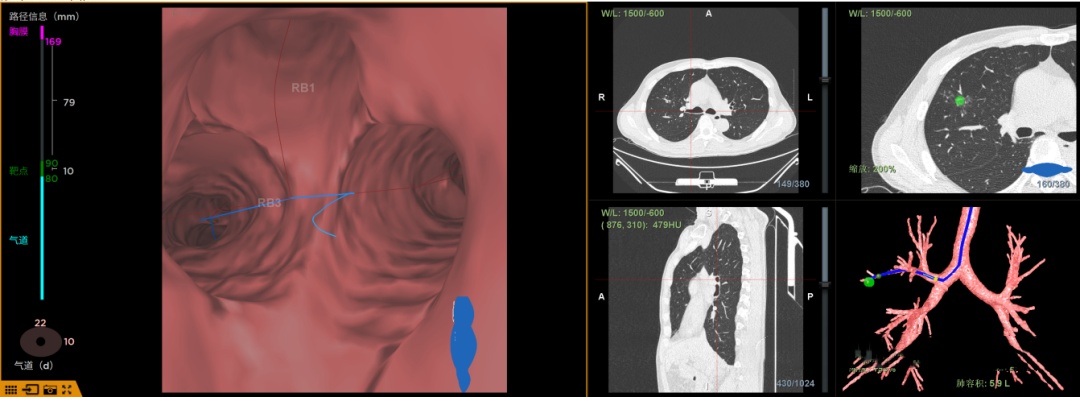

术中实况

2. 术中实时锥形束CT扫描: 堪称手术中的“鹰眼”。在支气管镜行进过程中或消融前,可即时进行锥形束CT扫描,如同开启实时卫星定位,确认器械是否精准抵近靶点,并监测消融范围是否完全覆盖目标结节,确保治疗无遗漏。